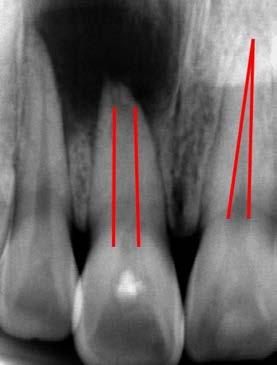

Figura 1. Fotografías intraorales y lateral de cráneo. A. Vista lateral (VL) derecha en oclusión. B. Vista frontal (VF) en oclusión. C. VL izquierda en oclusión. D. Radiografía lateral de cráneo.

Reporte de caso clínico

Paciente masculino de 10 años, se presenta a la consulta en la clínica Gnathos, la mamá reporta desagrado en la estética dental y facial del paciente. En la exploración clínica se observa mordida profunda, amplio número de piezas dentales con caries, fracturas dentales, mala higiene y encías inflamadas. presenta clase II división 2, se le indicaron estudios complementarios para diagnóstico asertivo, modelos de estudio,

Tratamiento de mordida profunda

radiografía panorámica y lateral de cráneo, fotografía intraoral y extraoral, historia clínica y consentimiento informado.